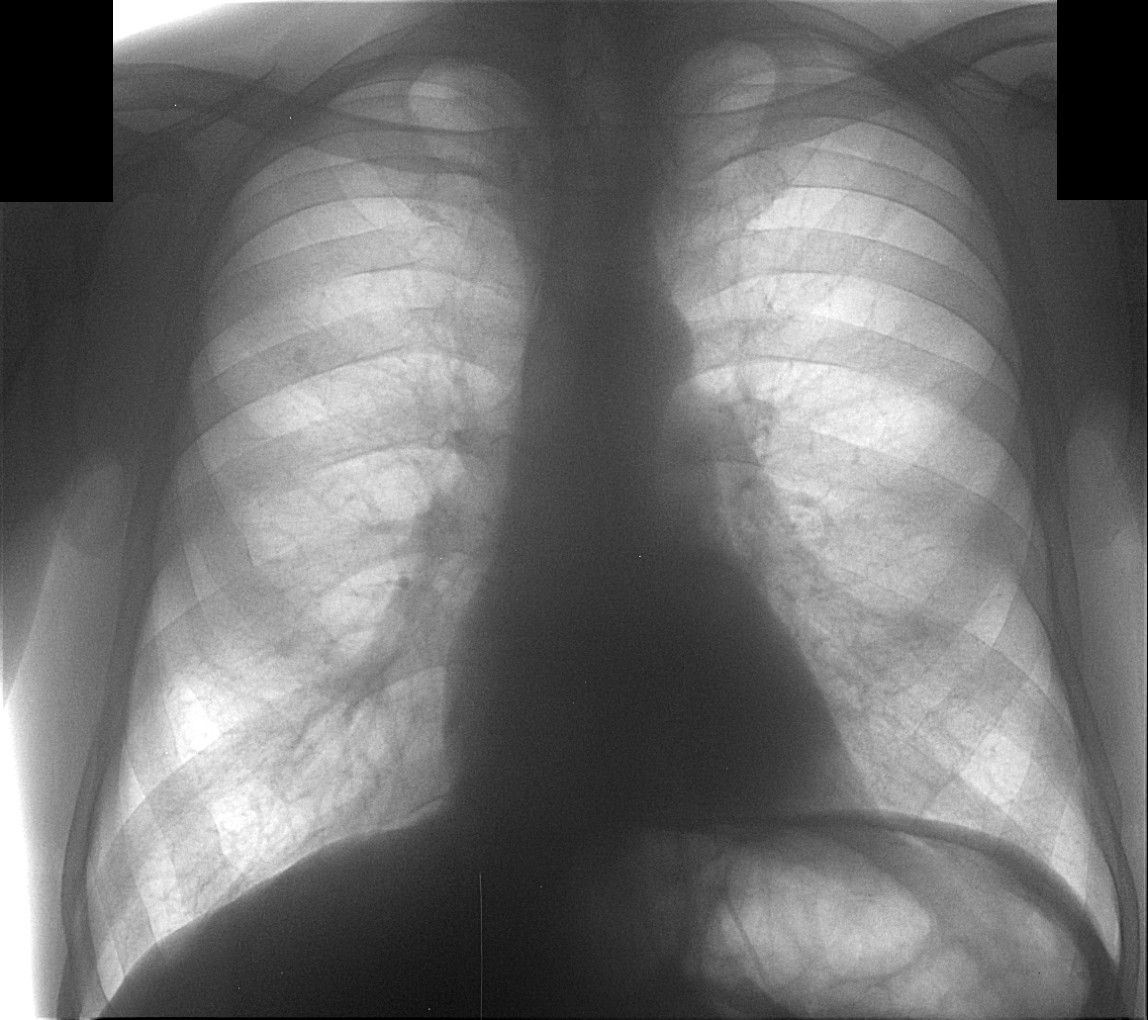

Liev_bokov.jpg

Через 10 дней направлен повторно, диагноз - пневмония слева. Прямой снимок без признаков инфильтрации, учитывая клинику (интоксикация, гектическая температура, боль в лев. половине гр. кл.), решили посмотреть за сердцем в лев. косом положении, лев. боковой сам Бог велел (снимки представлены). Посмотрели и скопически: в S10 инфильтрация с участками просветления, в заключении написали - пневмония, но термин "абсцедирование" решили не применять, хотя "в уме держали". Больного направили в т/о, там почему-то усомнились в нашей диагностике, пациент вернулся: "меня направляют на Р-гр". Пришлось связаться с терапевтами и прочитать лекцию о том, кто и за что отвечает. На следующий день терапевты с завидным упрямством настаивают на контрольной Р-гр., говорят - боимся абсцедирования, хорошо - говорю, договариваюсь с кэтэшниками, "прокатили" грудную клетку. Но ничего нового, дополнительного не нашли, а "просветлениями" оказались просветы бронхов. Инфильтрация расположена пристеночно, прилежит к позвоночнику с переходом на заднюю стенку гр. клетки, именно в связи с этим никак не прявляет себя на прямом снимке и на боковом выглядит не слишком убедительно. Наиболее оптимальными для такого расположения являются передняя левая или задняя правая косые проекции. Еще через 10 дней, при контрольной рентгеноргафии (прямая и левая боковая), картина без признаков инфильтрации, зная особенности случая, беру за экран и при указанных выше положениях вижу остатки инфильтрации, трактую как "остаточные изменения после пневмонии". Клинически - пациент бъет себя в грудь: "все прекрасно, домой хочу!".

Иконка изображения Liev_bokov.jpg156.82 КБ

Сие наблюдение нашего коллеги врача - рентгенолога В.Б. Серова весьма показательно по следующим обстоятельствам: 1. В настоящее время во многих лечебных учреждениях, как среди врачей клиницистов, так и среди части врачей рентгенологов, бытует мнение, что рентгеноскопия – рентгенотелевидение, при исследовании пациентов с «легочной патологией» себя изжило, и в ряде лечебных учреждений данные исследования отданы в руки рентгенолаборантов, а врачи рентгенологи на следующий день «пишут рентгенографическую продукцию» (я ещё раз подчеркиваю, что «в ряде лечебных учреждений». И очень отрадно, что врачи – рентгенологи, используя полипозиционную рентгеноскопию – рентгенотелевидение обоснованно безусловно, как демонстрирует данный случай (за сердечной тенью) визуализируют паторлогический процесс, который задокументирован на левой боковой рентгенограмме. 2. Довольно типично для врачей терапевтов, да и врачей хирургов, что свидетельствует об отсутствии этики и деонтологии, а также о коллегиальности, «усомниться в заключении рентгенолога». Чаще всего это связано с амбициями, а в ряде случаев, что встречается более часто с потерей именно терапевтами навыков аускультации, перкуссии, и нежелании инспектировать больного согласно принятой схеме стандарта. И что интересно терапевты считают, что они очень хорошо разбираются в рентгенологии и вообще «параклинике» и также «не доверяют» врачам лаборантам, но почему – то стекол не пересматривают, а вот рентгенограмму «посмотреть» на фоне окна и деревьев, видимых из этого окна – весьма эффектно, особенно, когда рядом находится пациент. 3. Очень интересная тактика обследования на следующий день на КТ, а не в динамике (это безусловно свидетельство безалаберности и попустительства начмеда). В связи с этим немного в сторону – мне очень нравятся врачи КТ и их разновидности, которые перед исследованием ОГК, требуют произведенные в рентген-кабинете снимки- рентгенограммы и линейные томограммы. Интересно зачем, если КТ-шные методики считаются более информативными. 4. Уважаемый коллега! Я с Вами не соглашусь, что на левой боковой рентгенограмме инфильтрация выглядит неубедительно, по – моему довольно убедительно, но конечно это субъективно. 5. С Вами невозможно не согласиться, по поводу остаточных изменений, и довольно часто, как вы указываете, мы наблюдаем «фрагменты ранее определявшейся инфильтрации», что даже в нашей литературе трактуется, как «остаточные явления», хотя каждый рентгенолог прекрасно понимает, что до восстановления структуры еще далеко. То что в данный период терапевты «уже ничего не слышат» - все хорошо, не говорит ни о чем, они весьма часто и стадиях опеченения «ничего не находят».

"Я с Вами не соглашусь, что на левой боковой рентгенограмме инфильтрация выглядит неубедительно.."

Неубедительно для "непосвященных" и непросвещенных, вы же знаете, им надо "картинку из учебника". А вот на контрольной лев. боковой рентгенограмме, действительно, инфильтрация совершенно не дифференцируется, жаль не сфоткал, не было цифровика с собой, теперь, помня о вашем пожелании "нам более часто необходимо обмениваться, именно на сайте, случаями из практики", постараюсь таскать фотик. Так всегда :-( когда случай предоставляется - нет с собой фотоаппарата. А из флюорографа могу натаскать много картинок.